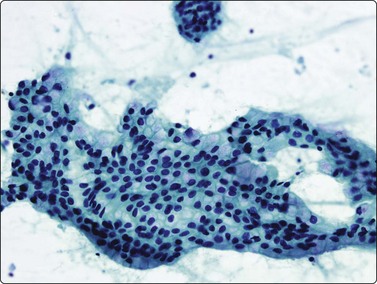

Fig. 8.24 Primary adenocarcinoma

Strong positive nuclear staining for TTF-1 (Cell block, IPOX, HP).

There are no absolute cytological criteria for separating primary from secondary adenocarcinomas, although there may be features indicative of a particular organ of origin (see Chapter 5). Immunostaining for TTF-1 provides the best single marker of a primary origin (Fig. 8.24), although it should be recognised that metastic thyroid malignancies and occasionally metastases from other sites may be TTF-1 positive.144-146